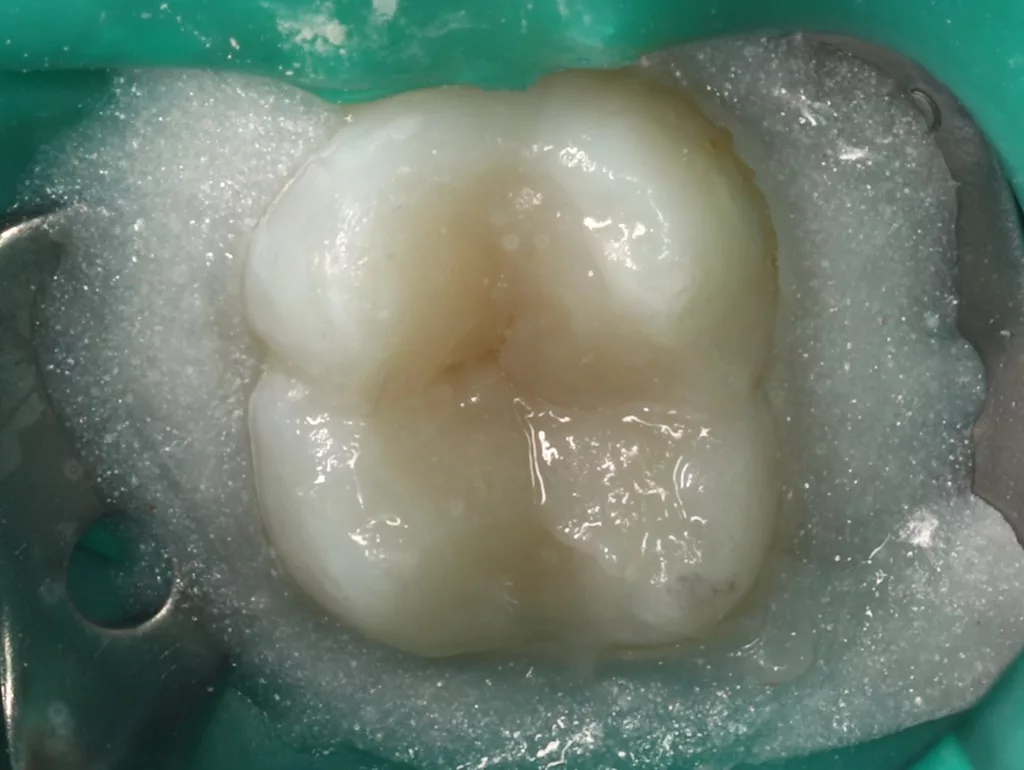

Das fünfjährige Mädchen stellte sich 2017 zur jährlichen Routinekontrolle vor. Im Rahmen der Untersuchung wurden Röntgenaufnahmen der Milchmolaren gemacht (Abb. 2). Der klinische und radiologische Befund der vor uns früher gelegten Kompositfüllungen war gut, es wurde allerdings eine PEIR an den noch nicht durchgebrochenen ersten bleibenden Molaren festgestellt (Abb. 2). Den Eltern wurde empfohlen, sich unverzüglich bei Beginn des Durchbruchs der ersten Molaren erneut zur Behandlung vorzustellen. Ein Jahr später erschien die junge Patientin schmerzfrei zur Kontrolle. Der Zahn 36 war noch teilweise mit Gingiva bedeckt. Auf einer neuen Röntgenaufnahme (Abb. 1) wurde die PEIR-Läsion mit unveränderter Größe in pulpanahen Bereichen bestätigt (Grad 3 der Läsion nach Seow). Der Zahnschmelz sah intakt aus, es konnte kein pathologischer periapikaler Befund bei den noch nicht ausgewachsenen Zahnwurzeln festgestellt werden. Daraufhin wurden die verschiedenen Behandlungsmöglichkeiten von Fissurenversiegelung bis Vitalerhaltung der Zahnpulpa mit den Eltern des Kindes besprochen.

Unter Lokalanästhesie mit dem STA-System (Milestone Scientific, USA) und Septanest 1/200 000 (Septodont, Frankreich) wurde die überstehende Gingiva mit dem Khors Koagulator (Эctatex, Ukraine) koaguliert und der Bereich unter Kofferdam kontaminationsfrei dargestellt (Klammer U67, KSK Dentech, Japan). Die schmalen Fissuren wurden mit dem Fissurenbohrer CD-53F (Mani, Japan) erweitert, um anschließend mittels RONDOflex plus 360 (KaVo Dental, Deutschland) und Pulver 27 µm vollständig gereinigt werden zu können. Es konnte weder durch visuelle Inspektion noch Sondierung mit 0.08 H-file (Mani, Japan) ein Defekt des Zahnschmelzes festgestellt werden. Unter Berücksichtigung der Integrität des Zahnschmelzes, der Symptomlosigkeit, des Behandlungszeitpunktes, Alters des Kindes und Wachstums der Zahnwurzeln fiel gemeinsam mit den Eltern die Wahl auf eine konservative Therapie. Es wurde eine Fissurenversiegelung mit Clinpro Sealant (3M, USA) unter Anwendung eines adhäsiven Behandlungsprotokolls mit Optibond FL (Kerr, USA) durchgeführt. Dieser klinische Fall ist dahingehend einzigartig, da alle anderen ersten und zweiten Molaren des Kindes ebenso von einer PEIR betroffen waren (Grad 1 bis 2 der Läsion nach Seow) (Abb. 3 und 12). Normallerweise ist nur ein Zahn bei einer Patientin oder einem Patienten betroffen. Die Zahnkronen der anderen betroffenen Zähne erwiesen sich bei der klinischen Untersuchung als intakt; die radioluzenten Läsionen innerhalb des koronalen Dentingewebes waren wesentlich kleiner als die von Zahn 36. Daher wurde auch bei diesen Molaren das gleiche Behandlungsprotokoll angewendet und nur eine Fissurenversiegelung durchgeführt.